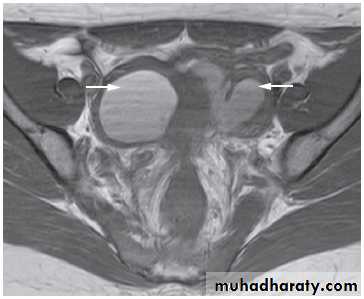

On MRI There are characteristic appearances due to recurrent haemorrhage into endometriomas and there is often in-drawing of the rectum towards the pouch of Douglas due to the development of fibrous adhesions.